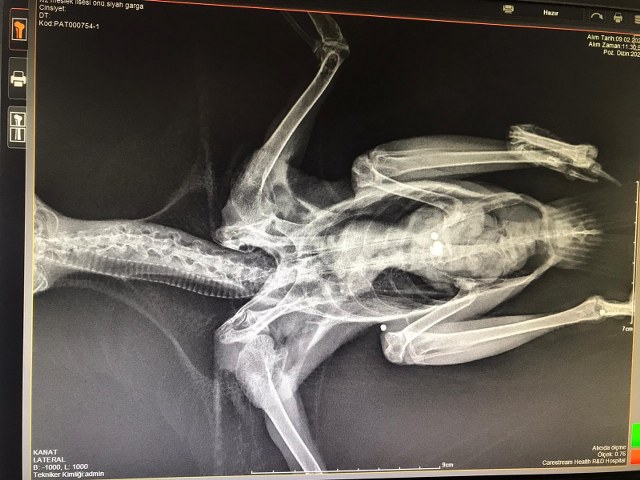

Muğla’nın Menteşe ilçesinde yaralı halde bulunan karga Muğla Büyükşehir Belediyesi Geçici Hayvan Bakımevi’ne getirilerek tedavi altına alındı. Yapılan muayene sonrası karganın belirli bölgelerinde ciddi yaralanmalar tespit ettiklerini söyleyen Muğla Büyükşehir Belediyesi Geçici Hayvan Bakımevi ekipleri hemen karganın röntgenini çektiklerini, ateşli silahla yaralandığını, vücudunun çeşitli yerlerinde 3 adet saçma bulunduğunu ve kanadının da kırık olduğunu tespit ettiklerini belirttiler. Ameliyata alınan karga saçmalardan kurtarılarak müşahede altına alındı. Muğla Büyükşehir Belediyesi Geçici Hayvan Bakımevi’nde iyileşme süreci takip edilecek karganın tamamen iyileştikten sonra doğaya salınacak. (HABER MERKEZİ)